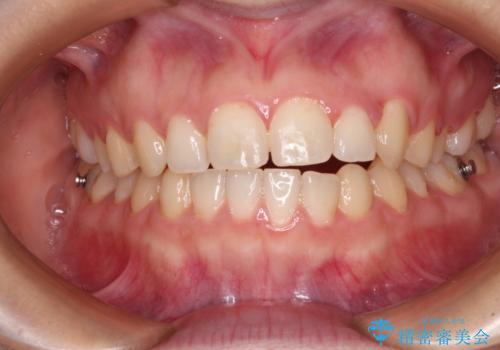

気になる残存乳歯と八重歯 ワイヤー矯正を併用したインビザライン治療

- 八重歯を気にして来院された患者様です。

八重歯のために乳歯が残存していたため、乳歯を抜去して八重歯となっている犬歯を歯列に収めることとしました。

八重歯の移動量が多くなるため、インビザラインと併用してワイヤー矯正を行い、八重歯を改善した後に、上下歯列をインビザラインで整えることとしました。

犬歯は歯根が長くて太いため移動に時間がかかる上に、周囲の歯が八重歯に寄ってきてしまうため、仕上がるまでに期間がかかりました。